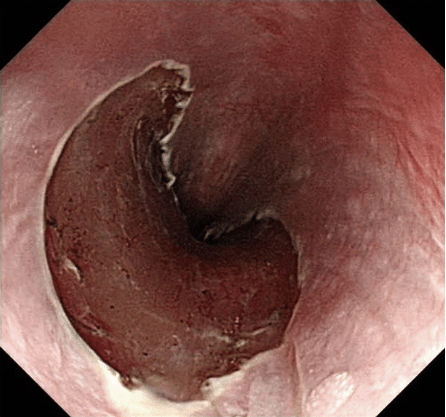

图1 碘染色可观察到不着色区域为早期食管癌部位